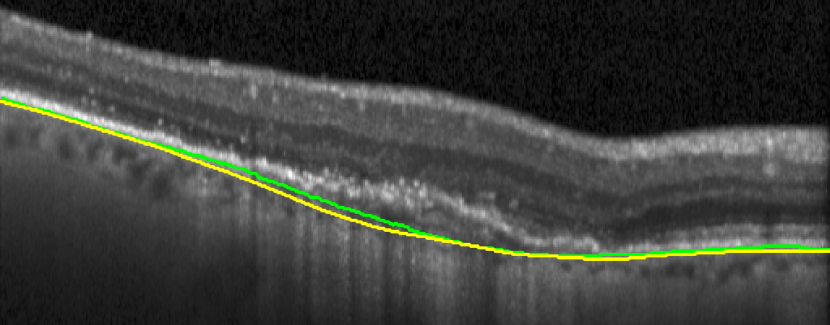

(a) Before TPS

(b) After TPS

II-C Post-processing with thin plate splines

We use a thin plate spline (TPS) [37] interpolation on the volumetric 3D OCT scan to estimate a viable position of the BM in the uncertain areas. The TPS finds an interpolating surface with a set of control points to assure minimum bending of the BM. With TPS, we replace the uncertain BM positions with their interpolated values.